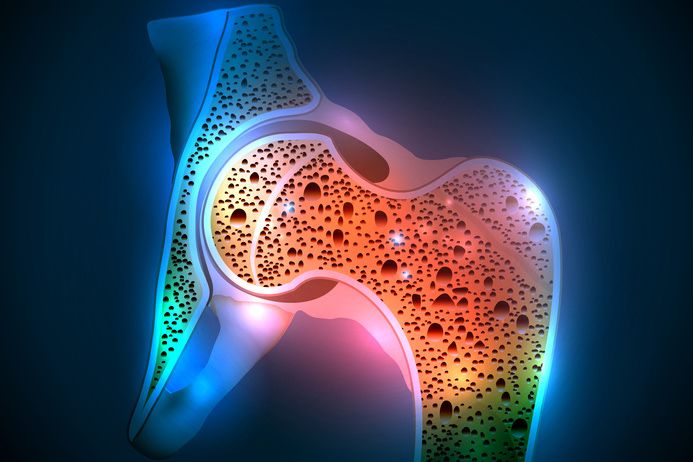

Osteoporosis is a systemic condition characterised by a reduction in bone mass and changes in the micro-architecture of bone tissue. This reduces bone strength and increases the risk of bone fractures. It affects around 200 million people worldwide and forecasts indicate that it will become more prevalent in future. In order to reverse this trend, more attention must be paid to information, prevention, prompt diagnosis and appropriate treatments.